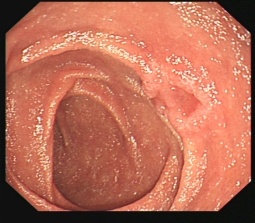

消化道早癌的病例展示(经内镜手术或活检证实):

十二指肠降段早癌